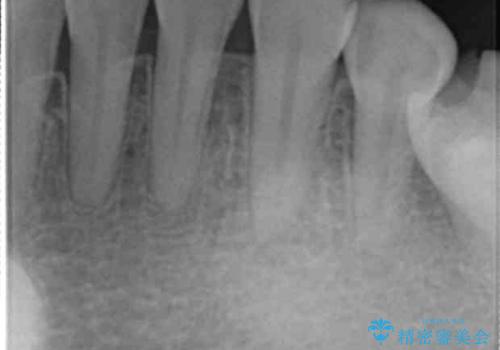

CTでみたところ、下の犬歯が内側に倒れこんでおり、根の先が顎の骨から出かかっている状態でした。おそらくその影響で犬歯の神経が失活してしまったのであろうと思われます。(フェネストレーションといいます)

検査した結果下の両側の犬歯の神経が失活しており、根の治療が必要な状態でした。

矯正専門の医院でCTまで完備しているというのはなかなか施設の規模として難しいと思います。

また、矯正医が気付かずにすき間をとじようとして犬歯が倒れてしまうと今回のようなことが後々時々起こります。

一見歯がきれいに並んでいても、中の根の先の位置までしっかり矯正治療で丁寧に動かさないと、今回のように神経が失活するリスクがあるので、注意が必要です。